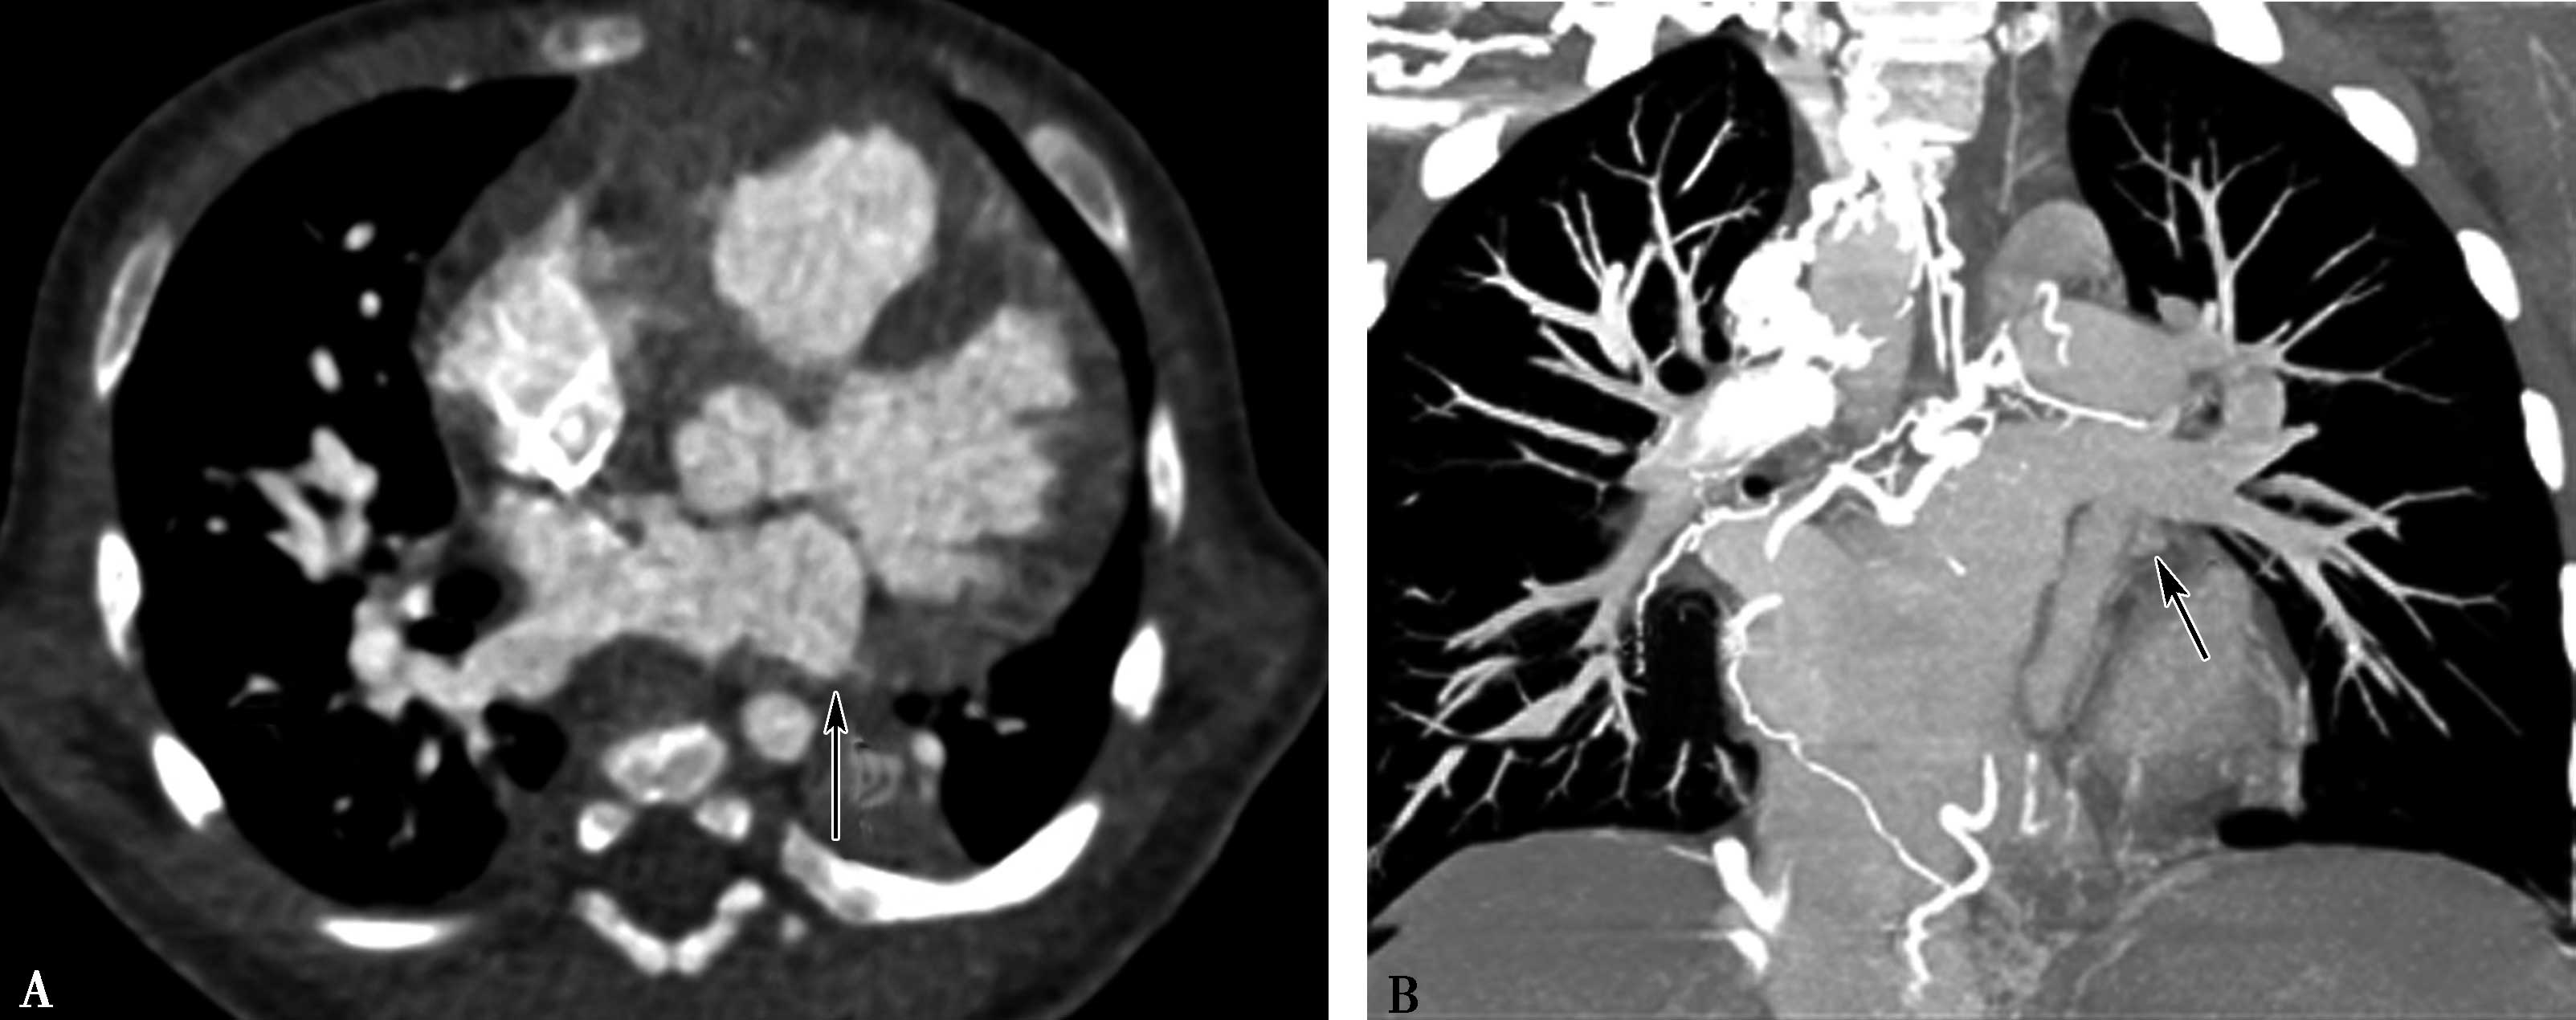

3.CT双能量成像技术应用于肺动脉造影成像时,可以采用自动识别彩色编码功能,能够对血管进行选择性色彩编码,从而提示可能的发生栓塞的肺血管,尤其是细小的肺血管,从而提高微小栓子的检出率,降低漏诊率(图8-1-10)。

图8-1-10 双源CT双能成像,显示左肺舌叶及下叶肺段及亚分段小分支栓塞,灌注缺损;彩色编码,使得图像清晰,利于观察,提高诊断检出率(↑)